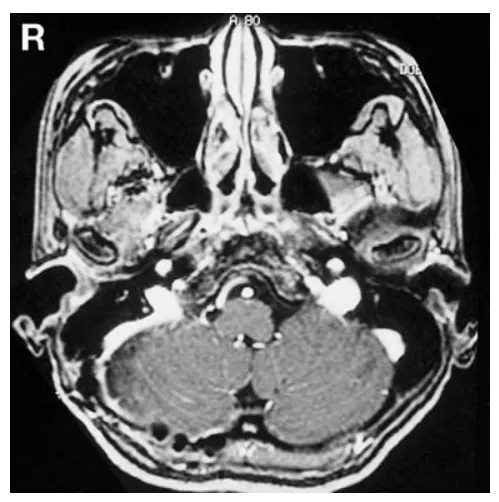

29岁女性患者小葵因听力丧失就诊,无其他神经功能缺损表现。初次磁共振成像检查显示右侧桥小脑角区存在直径3.5厘米囊实性强化占位病变,压迫脑干结构,但未明显侵犯内耳道或颈静脉孔(图1左、中)。骨窗计算机断层扫描检查显示内耳道无明显扩张(图1右)。

图1:术前轴位增强T1加权磁共振成像(左、中)显示右侧桥小脑角区占位性病变,未明显侵犯颈静脉孔。术前骨窗计算机断层扫描(右)显示内耳道无明显扩张。

幸运的是,患者小葵在出院前实用听力已恢复。术后1周纯音听阈测定证实其听力恢复(图2右)。术后8个月磁共振成像复查显示未见肿瘤复发(图3)。

图3:术后8个月轴位增强T1加权磁共振成像显示肿瘤无复发。